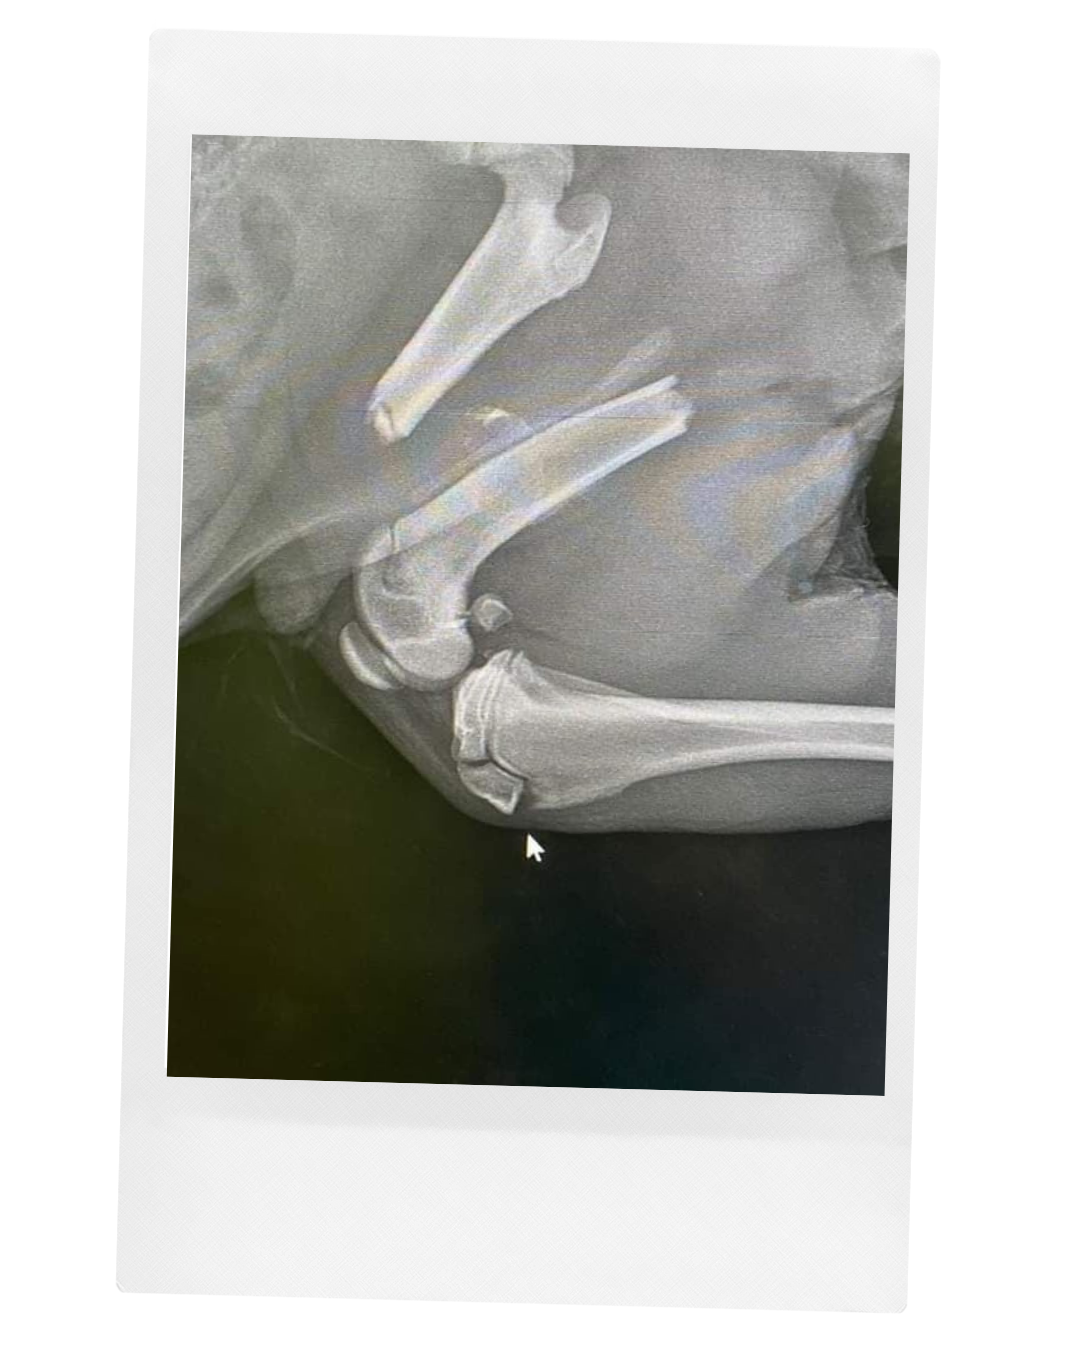

Jej príbeh sa začína veľmi smutne. Túto nádhernú a majestátnu fenočku zrazilo auto. Niekoľko dní ležala s otvorenou zlomeninou pri ceste, úplne sama, kým sa nenašiel človek so srdcom na pravom mieste, ktorý ju zdvihol a odviezol na veterinárnu kliniku.

Okrem komplikovanej zlomeniny bojovala aj s babeziózou. Je to choroba prenášaná kliešťom, ktorá býva často smrteľná. Sibra sa však nevzdávala a bojovala každý deň. Babeziózu sa podarilo vyliečiť v priebehu pár dní. Po šiestich mesiacoch náročných a opakovaných operácií sa nám podarilo zahojit aj jej zranenú nožičku.